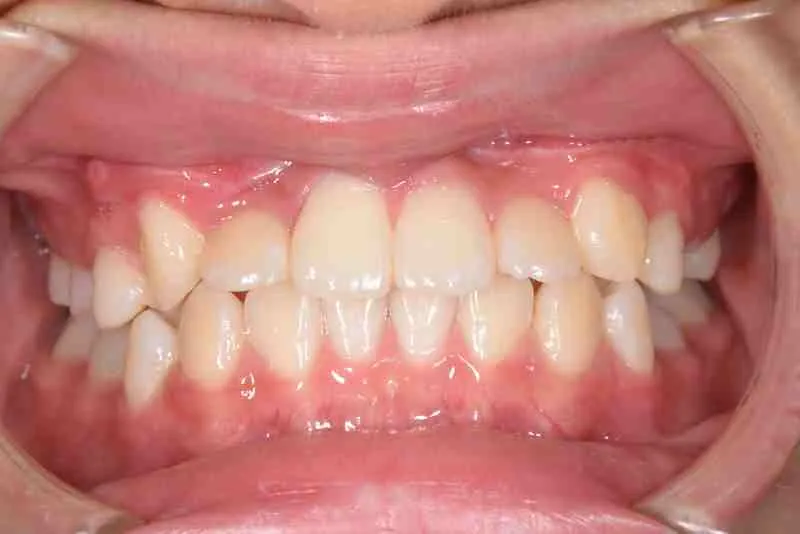

【子供の矯正(一期)】叢生・埋伏歯・受け口・永久歯が生える隙間がない・非抜歯症例・9歳女子【K.T様】

治療終了後

マルチブラケット装置は使わずに、最低限の必要な装置を使って目立たないように治療しました。

治療回数29回、2年10ヶ月の治療期間で矯正治療を終了しました。

主訴が改善され、ご満足頂きました。